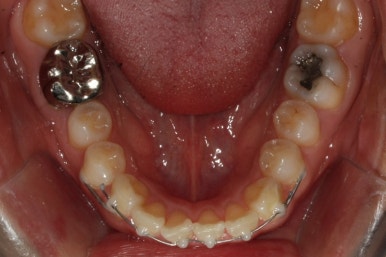

부산앞니교정 키다리아저씨치과에 처음 내원하셔쓸 당시의 입안 모습입니다.

앞니가 살짝 삐뚤어진 것을 볼 수 있고, 삐뚤어진 사이에서 약간의 틈새도 있었습니다.

예전에 치료 받으셨던 앞니 부분에 약간의 변색도 와서 미적으로 좋지 못한 상황이였습니다.